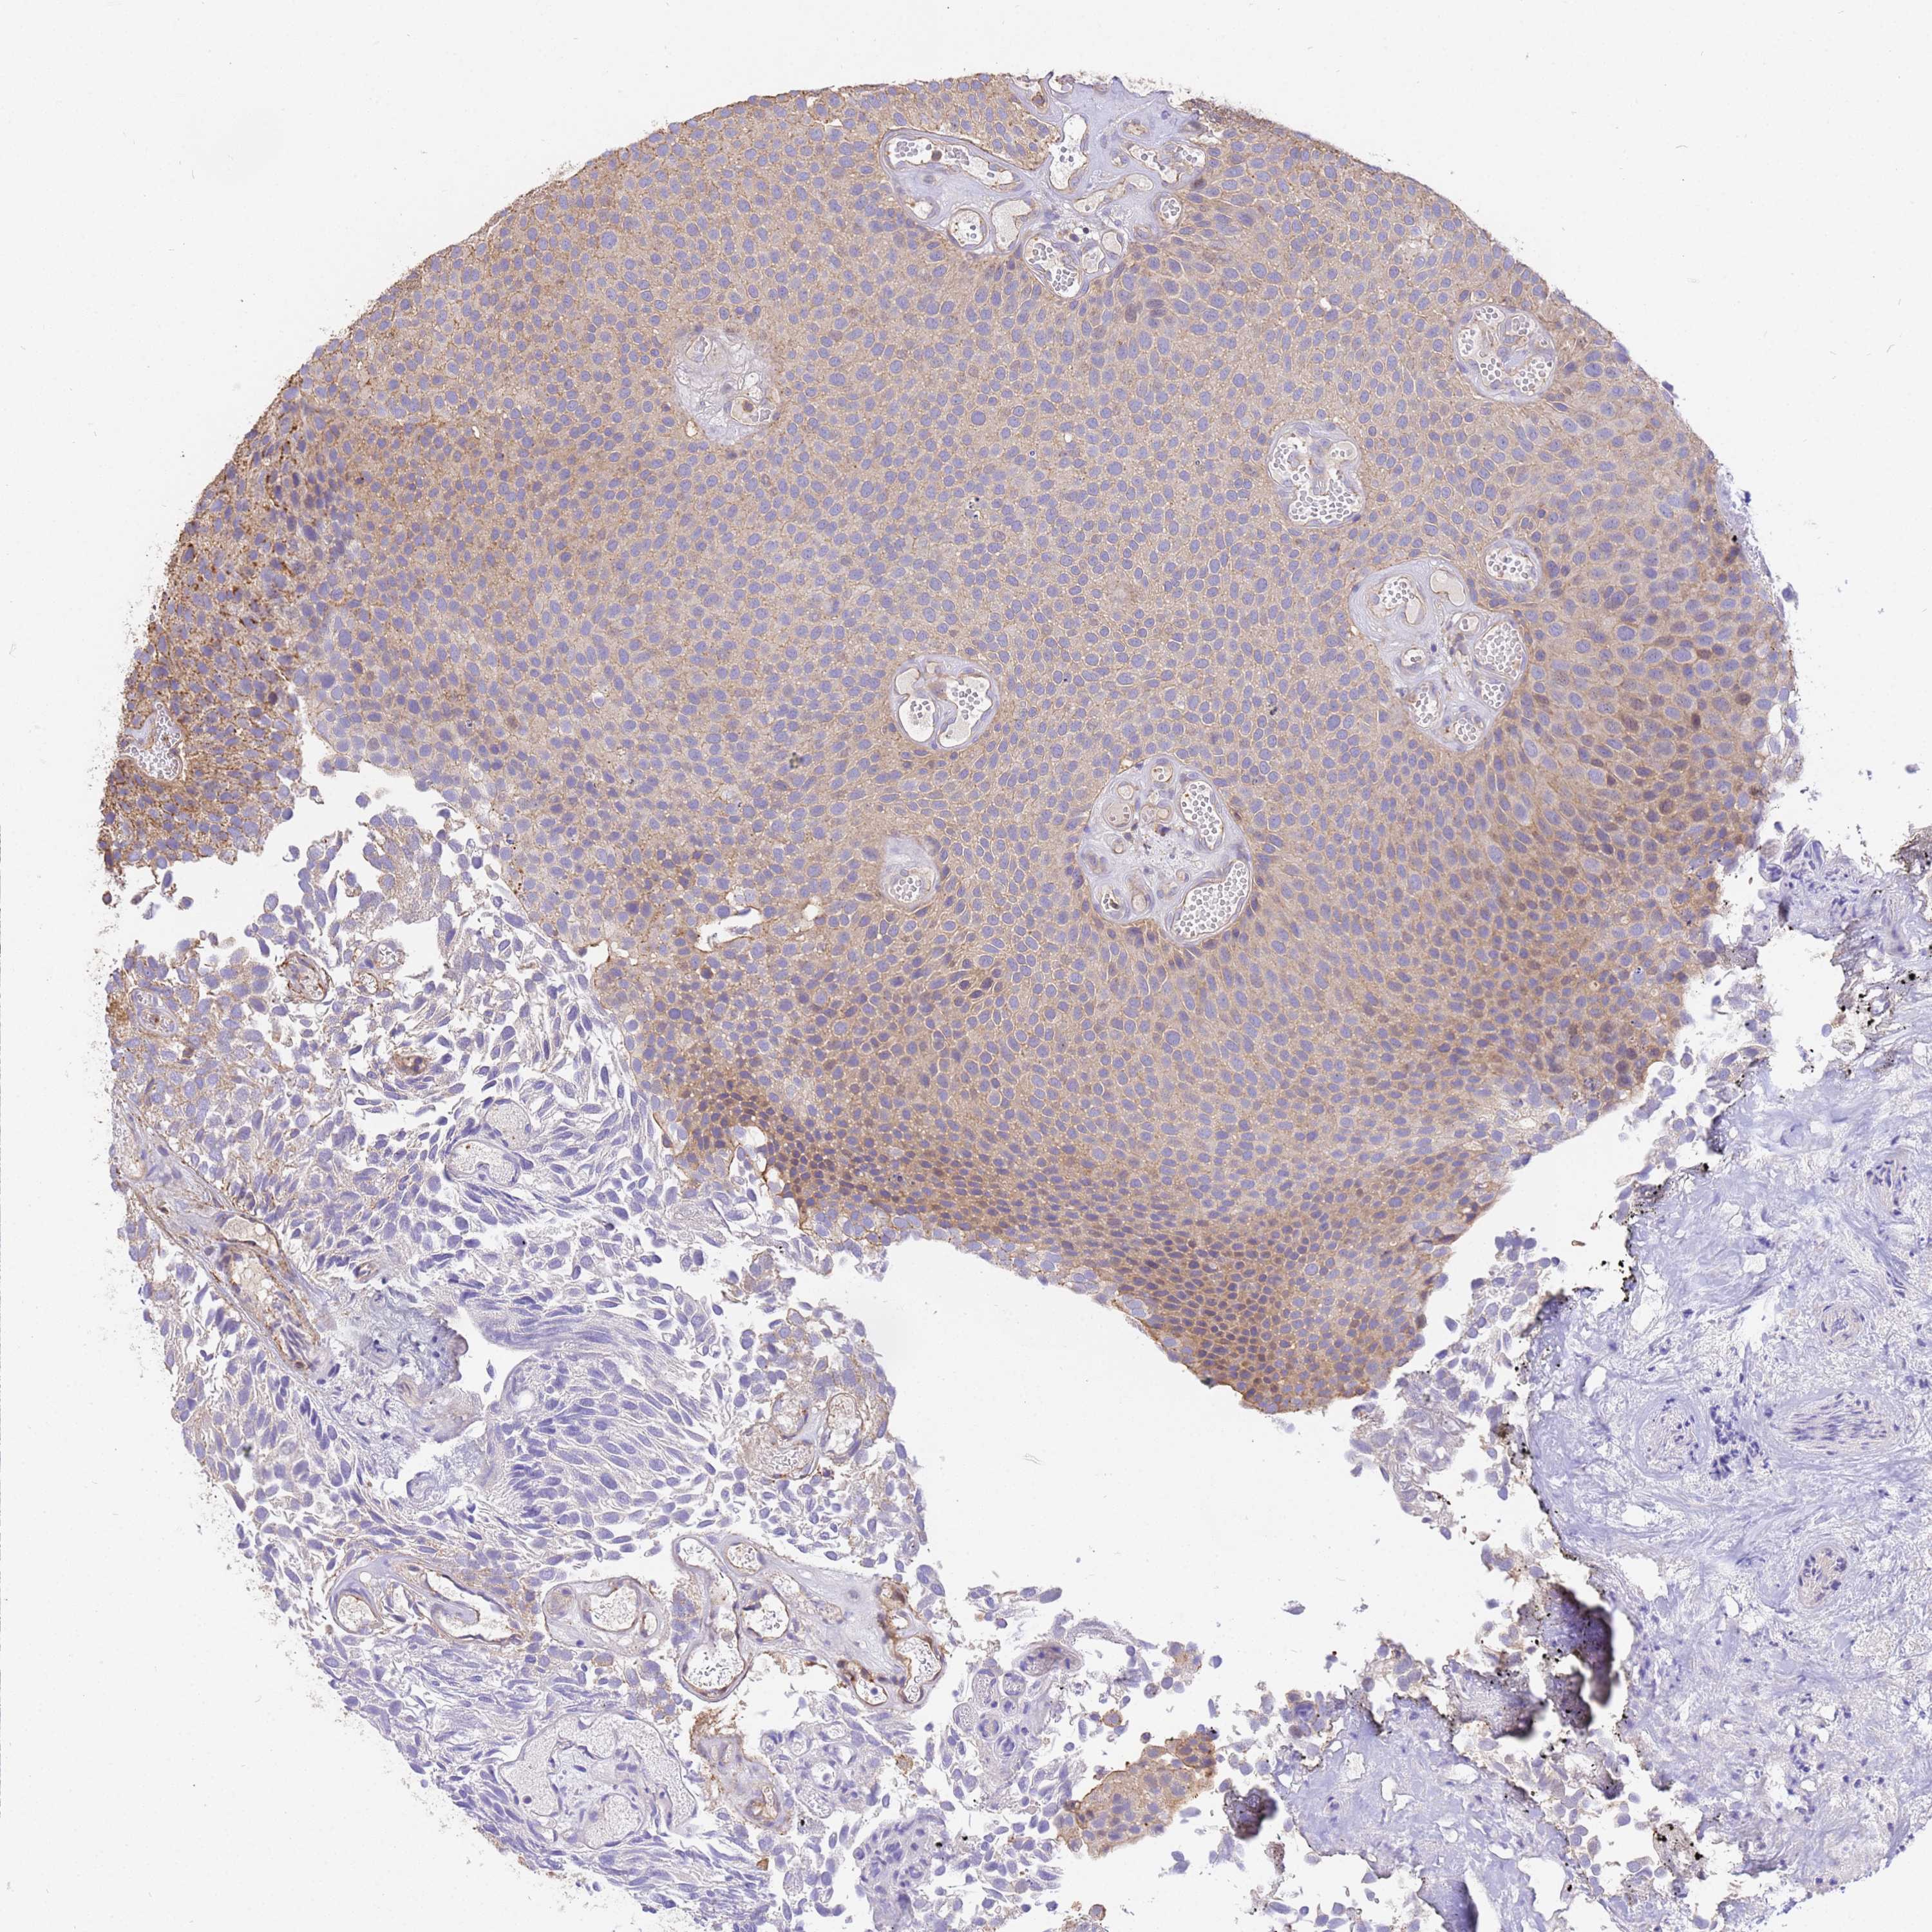

UROTHELIAL CANCER - Protein expressioni

A mouse-over function shows sample information and annotation data. Click on an image to view it in a full screen mode. Samples can be filtered based on level of antibody staining by selecting one or several of the following categories: high, medium, low and not detected. The assay and annotation is described here.

Note that samples used for immunohistochemistry by the Human Protein Atlas do not correspond to samples in the TCGA dataset.

Antibody stainingi

Antibody staining in the annotated cell types in the current human tissue is reported as not detected, low, medium, or high, based on conventional immunohistochemistry profiling in selected tissues. This score is based on the combination of the staining intensity and fraction of stained cells.

Each image is clickable and will lead to virtual microscopy that enables deeper exploration of all samples and also displays staining intensity scores, fraction scores and subcellular localization as well as patient and tissue information for each sample.

Antibody HPA046186

Staining

High

Medium

Low

Not detected

Intensity

Strong

Moderate

Weak

Negative

Quantity

>75%

75%-25%

<25%

None

Location

Nuclear

Cytoplasmic/membranous

Cytoplasmic/membranous,nuclear

Urothelial carcinoma, High grade

Urothelial carcinoma, Low grade